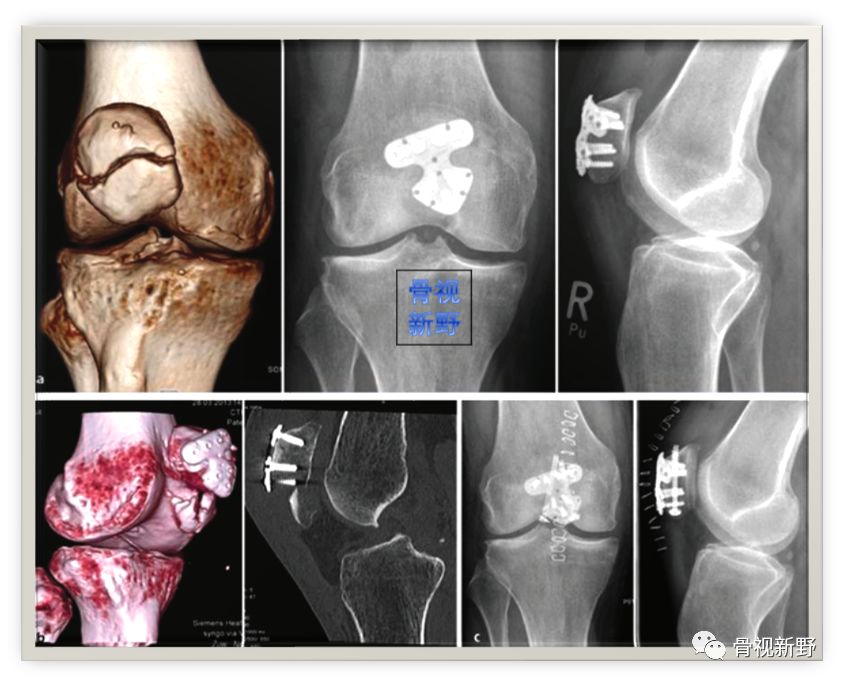

术中所见

X光所见

网状钢板

主要适用于包括下极在内的髌骨粉碎骨折的固定,对骨质疏松及髌骨骨不连者也较适用。

髌骨下极粉碎骨折的网状钢板固定及髌韧带加强缝合术。